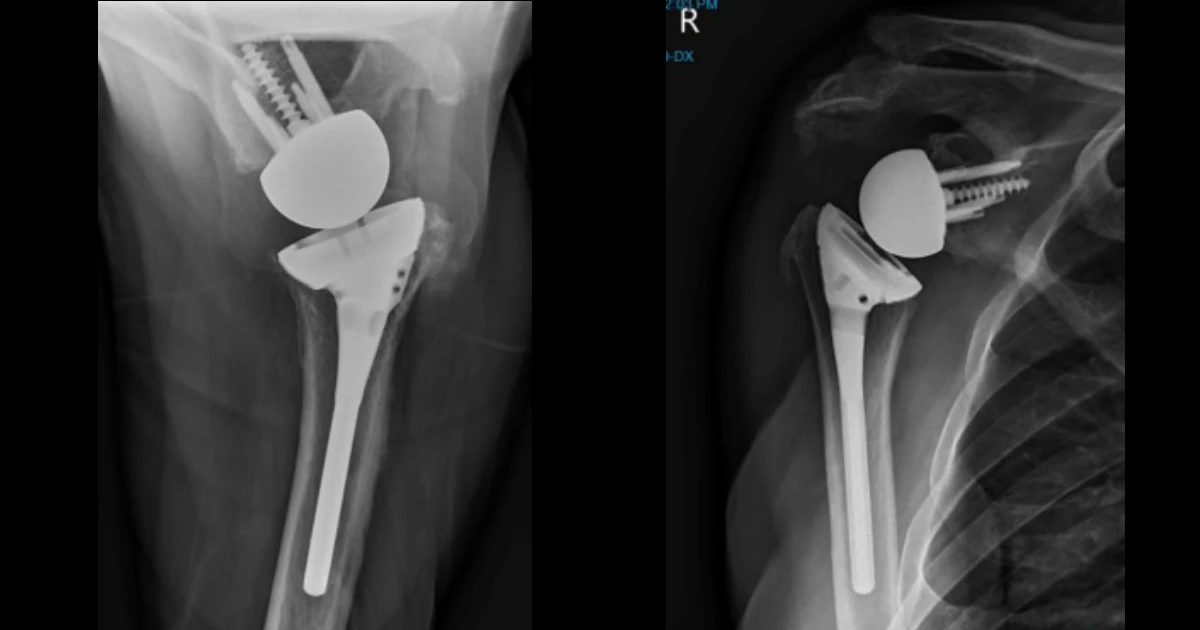

Post-operative X-rays showing the shoulder replacement in place

Peter subsequently underwent a right reverse shoulder arthroplasty. The procedure was performed through a standard deltopectoral approach. Intraoperative findings confirmed degenerative changes consistent with cuff arthropathy. The glenoid was prepared and fitted with a baseplate and glenosphere, while the humerus was prepared and fitted with a stem and polyethylene liner. Soft-tissue balancing was carefully performed, and a stable construct was achieved with restoration of shoulder biomechanics.